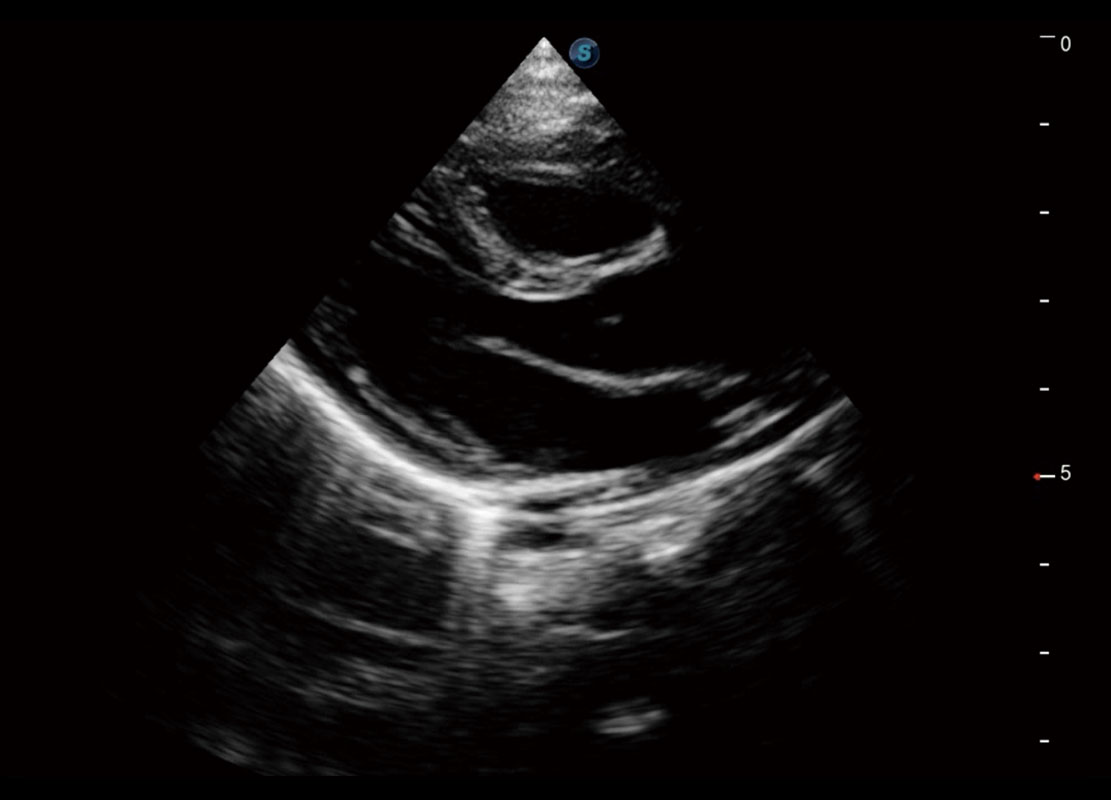

四腔切面

四腔心血流

右室双出口

胎心容积成像